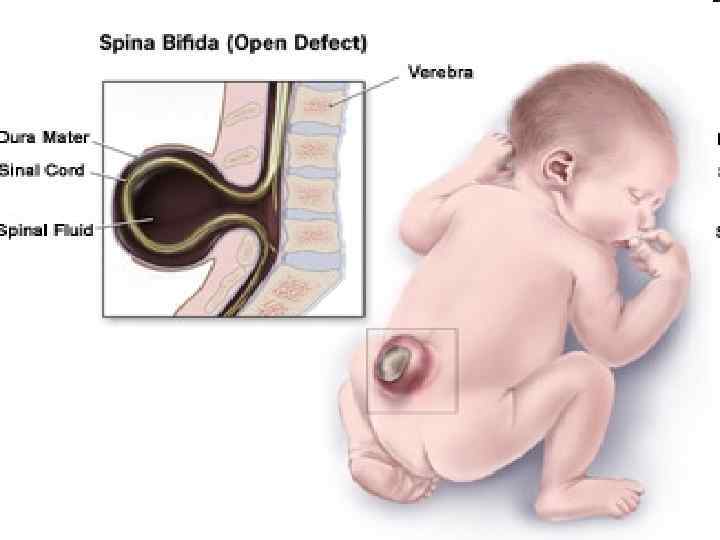

SPINA BIFIDA 111

Менингорадикулоцеле 112

Менингомиелоцеле 113

114

115

Ребенок со spina bifida 116